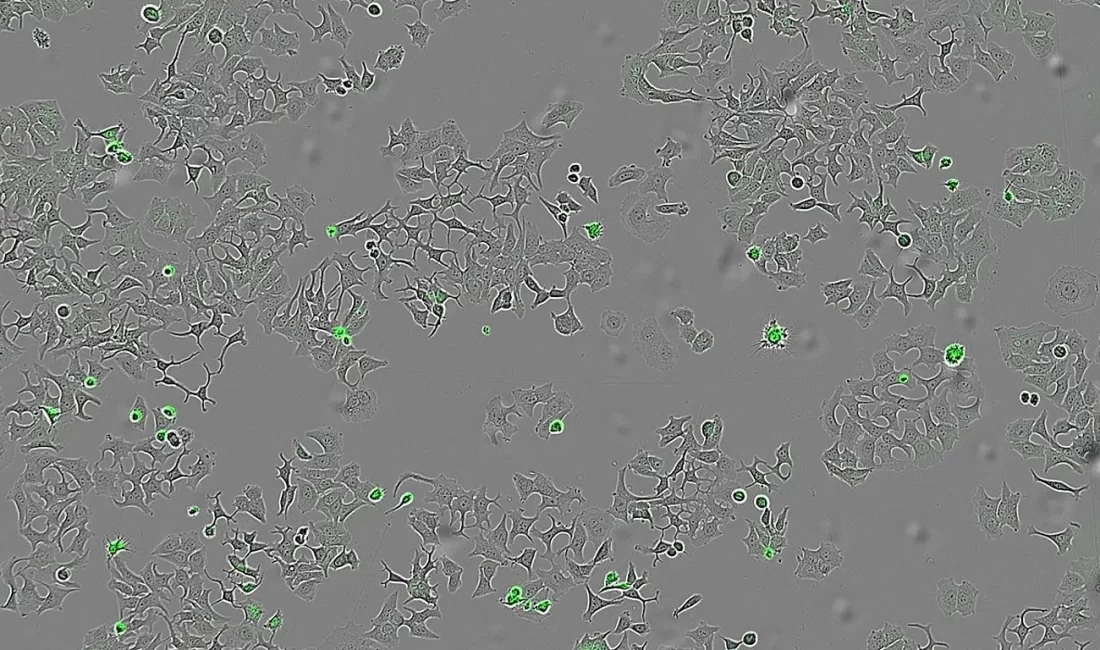

Bilim insanları, bu proteinin meme, kalın bağırsak ve pankreas kanseri hücreleri üzerinde etkili olduğunu belirledi. HapA, tümör hücrelerinin yüzeyinde bulunan PAR-1 ve PAR-2 reseptörlerine bağlanarak bu reseptörleri insan enzimlerinden farklı bir noktadan kesiyor ve hücreyi intihara sürüklüyor.

Deneylerde sonuç net: HapA proteini bulunan ortamlarda tümör hücreleri yok olurken, bu proteini üretmeyen bakterilerin bulunduğu ortamlarda hücrelerin yaşamaya devam ettiği gözlemlendi.